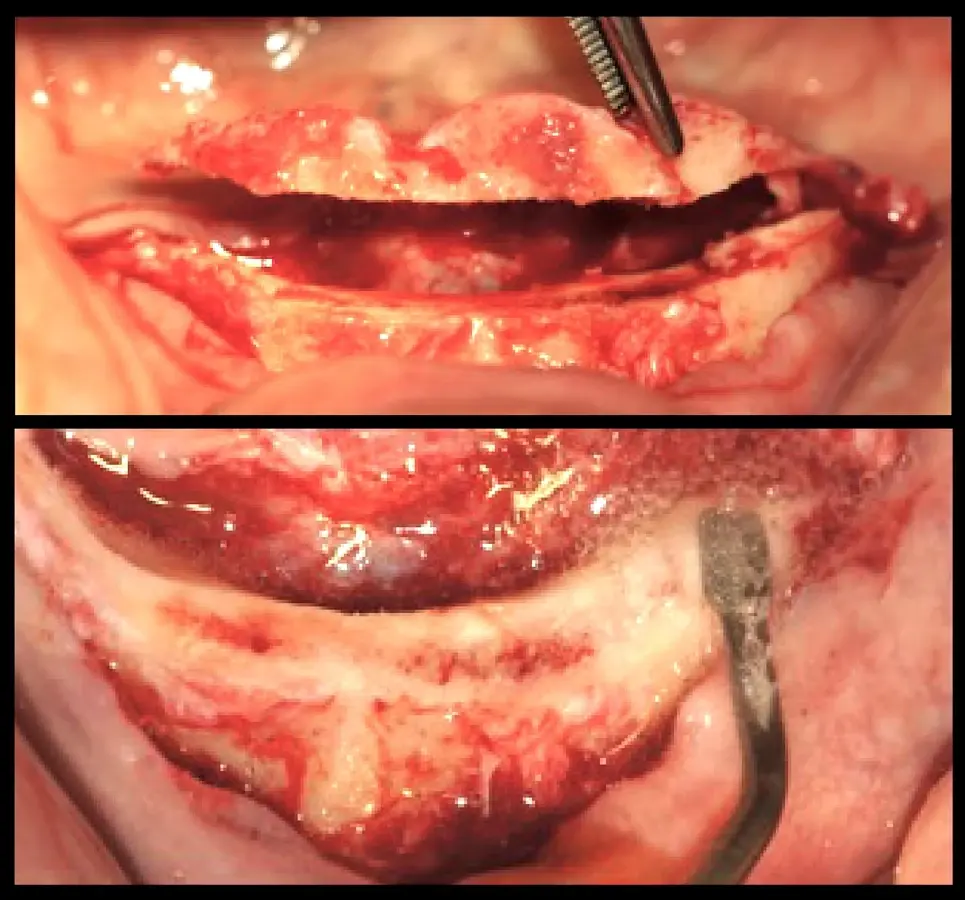

Se realizó la preparación del lecho periimplantar según el protocolo del fabricante (Unitite, S.I.N.). La secuencia de preparación de los implantes implicó la primera preparación del implante en posición C, en concordancia con la línea media del paciente, y que nos sirvió de guía para la preparación de los demás lechos quirúrgicos. Los siguientes lechos quirúrgicos preparados fueron los distales (Posición A y E); dicha preparación fue orientada hacia distal para mejorar la distancia antero-posterior y reducir así el efecto de palanca distal; finalizando con los de posición B y D. Se colocó la guía quirúrgica para revisar la emergencia en relación a la superficie oclusal de los dientes. La secuencia de fresado del fabricante (UNITITE, S.I.N.) es fresado intermedio, en donde el diámetro de la fresa final es 0.20 mm menor al diámetro del implante. El fresado intermedio reduce la cantidad de microfisuras a nivel de las roscas del implante, y favorece la neoformación ósea a nivel de las cámaras de cicatrización. Procedimos con la colocación de los implantes de 3.5 mm de diámetro y 10 mm de longitud (UNITITE, S.I.N.) (Figura 6).

La segunda fase quirúrgica y colocación de pilares intermedios fue realizada en la semana 18, siguiendo la recomendación del fabricante con un torque de 20 Ncm. Se realizó la impresión del maxilar superior y la transferencia de los implantes del maxilar inferior. Una vez corroborado el asentamiento de ambas estructuras en boca se envió al laboratorio para el enfilado de la estructura inferior. Finalizada la prótesis fue instalada en el paciente (Figura 10).